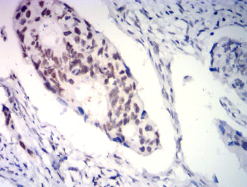

PGR Mouse Monoclonal antibody[2E4B9]

This gene encodes a member of the steroid receptor superfamily. The encoded protein mediates the physiological effects of progesterone, which plays a central role in reproductive events associated with the establishment and maintenance of pregnancy. This gene uses two distinct promotors and translation start sites in the first exon to produce several transcript variants, both protein coding and non-protein coding. Two of the isoforms (A and B) are identical except for an additional 165 amino acids found in the N-terminus of isoform B and mediate their own response genes and physiologic effects with little overlap.

Immunogen :   Purified recombinant fragment of human PGR (AA:166-411) expressed in E. Coli.

IHC    1/200-1/1000